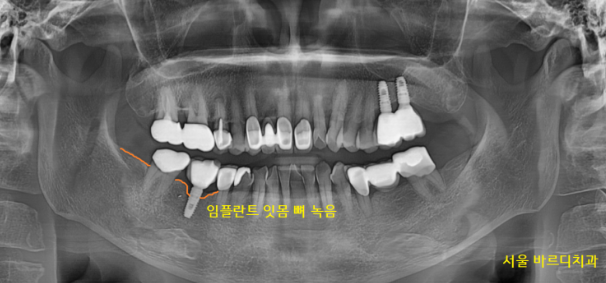

2020.11.04일 환자분께서

오른쪽 아래 잇몸이 불편하다고 내원해주셨어요.

자세히 살펴보니 임플란트를 했던 곳이

말썽이네요~

201104

예전에 다른 병원에서 임플란트를

수술받으셨다는데

하신지 오래되고 관리가 잘 안되다 보니

문제가 생겼습니다.

임플란트 주변 염증으로 인하여

잇몸 뼈가 녹아있었습니다.